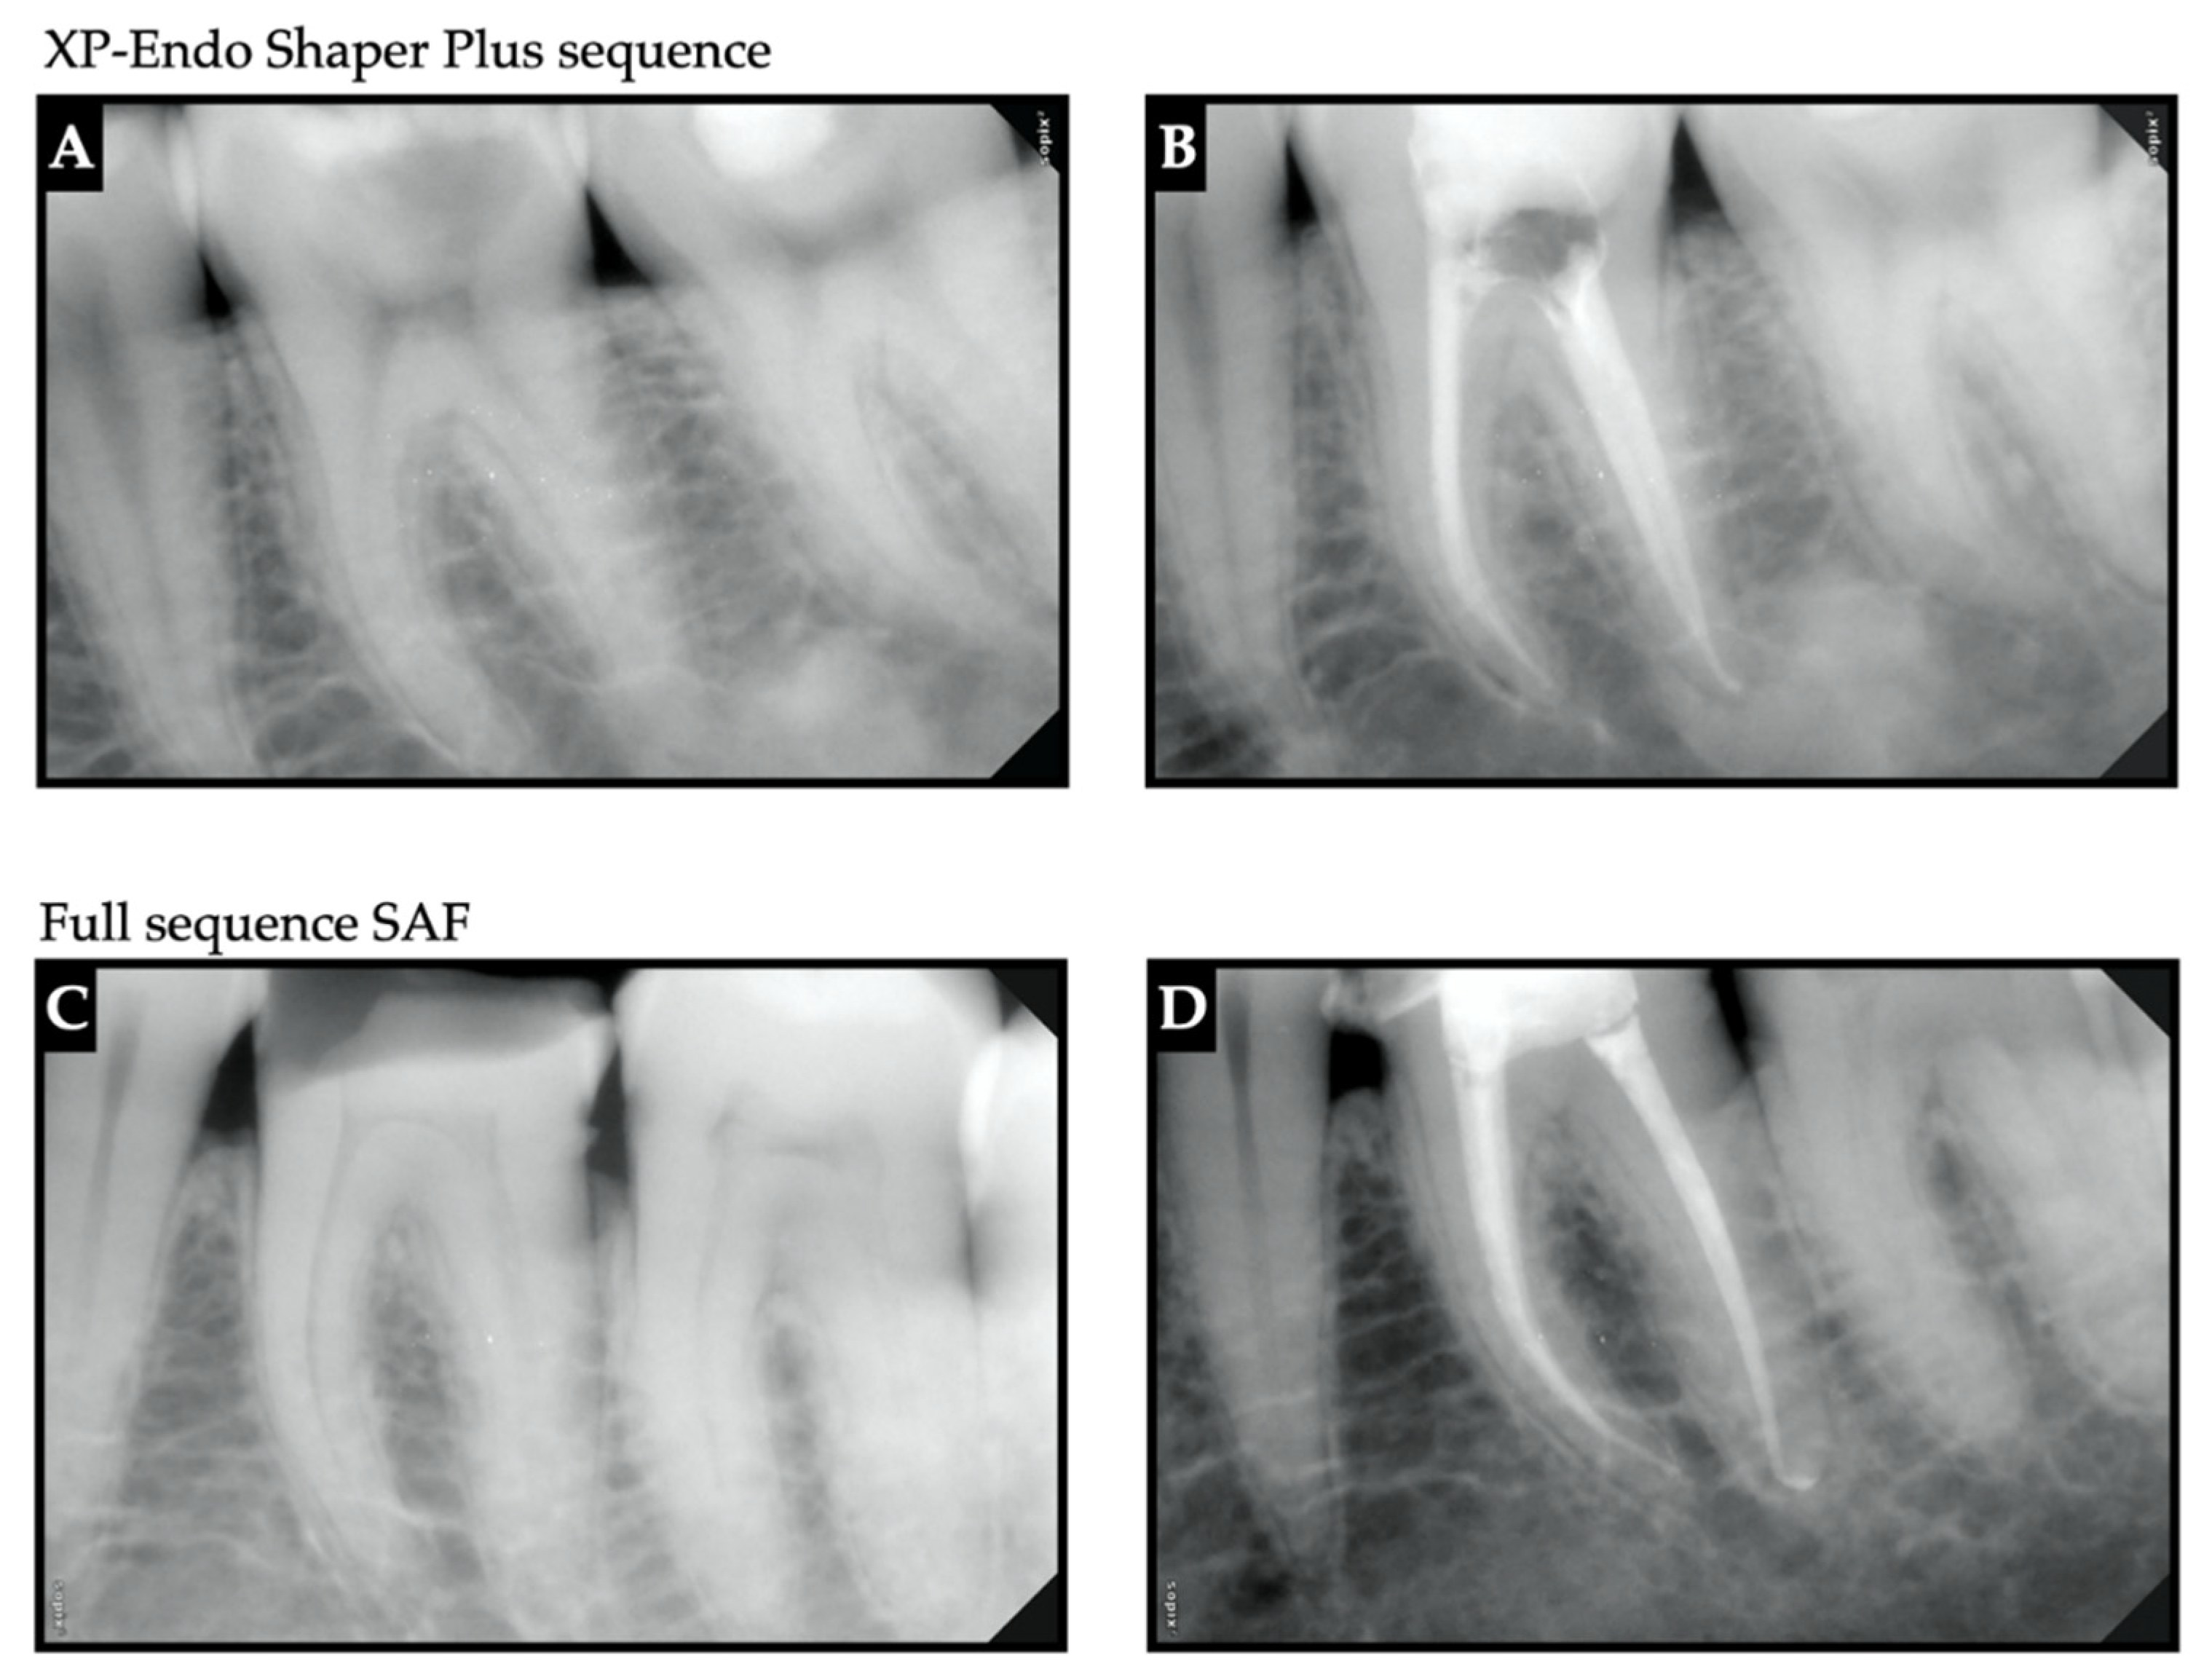

Figure 2. Representative radiovisiographs (RVGs) of pre-operative and post-obturation for XP-endo shaper plus sequence (mandibular second molar) (A,B) and full-sequence SAF (mandibular first molar) (C,D).

2.6. Root Canal Obturation